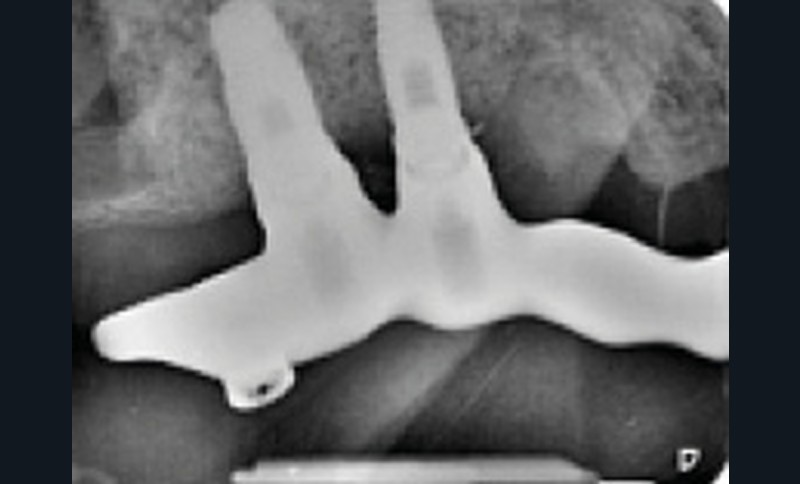

Une réhabilitation par PACSI maxillaire a été réalisée dix ans auparavant sur 5 implants en place de 13, 12, 21 et sur 24 et 26 (fig. 2a et b). Dans le cadre du plan de traitement initial, 6 implants avaient été indiqués. L’un d’entre eux, en position distale dans le secteur I, n’a jamais été ostéointégré. La patiente ne souhaitant plus de chirurgie, il avait donc été décidé de réaliser une prothèse sur 5 implants. La barre est directement connectée aux implants. À la mandibule, la patiente présente également une PACSI sur 2 implants associés à 2 piliers Locator®.

Lors de l’examen clinique, après dépose de la prothèse et dévissage de la barre, le constat est alarmant : présence de plaque abondante…